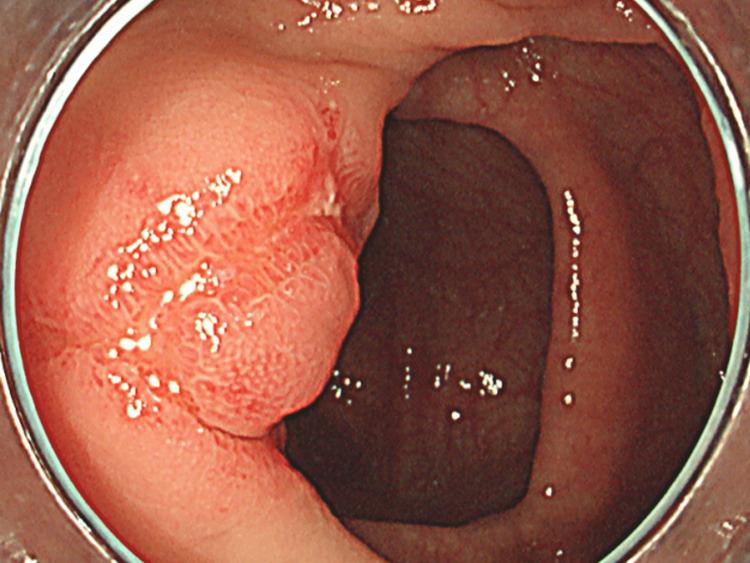

Eosinophilic gastroenteritis (EGE) is a disease involving the gastrointestinal tract that involves the invasion of eosinophils into the lumen of the tract. Invasion of eosinophils in the tract causes edema and inflammation of the wall, resulting in acute or chronic diarrhea and abdominal pain. EGE can cause chronic inflammation in the small intestine, thereby mimicking chronic vasculitis. We report the case of a 24-year-old male patient with the chief complaint of acute progressive abdominal pain. Endoscopic findings of the small intestine were chronic and similar to those of polyangiitis (eosinophilic granulomatosis with polyangiitis). This case shows the presence of various clinical courses of EGE and the discrepancy between the symptoms and endoscopic appearance of vasculitis. Physicians should focus not only on acute symptoms but also on chronic phases of the disease to prevent disease progression and modify patients' help-seeking behaviors according to their symptoms.

摘要

嗜酸性粒细胞性胃肠炎(EGE)是一种累及胃肠道的疾病,其特征为嗜酸性粒细胞侵入胃肠道管腔。嗜酸性粒细胞的侵入会导致肠壁水肿和炎症,进而引发急性或慢性腹泻及腹痛。EGE可导致小肠慢性炎症,从而类似慢性血管炎。我们报告一例以急性进行性腹痛为主诉的24岁男性患者。小肠内镜检查结果为慢性,与多血管炎(嗜酸性肉芽肿性多血管炎)相似。该病例显示了EGE存在多种临床病程,以及血管炎症状与内镜表现之间的差异。医生不仅应关注急性症状,还应关注疾病的慢性阶段,以防止疾病进展,并根据患者症状调整其就医行为。